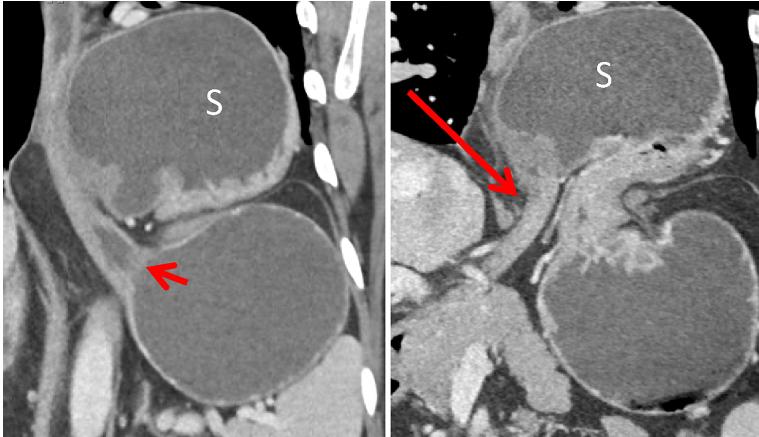

胃 套叠常 发生儿童,仅约 5%-16% 发生于成人,且 70%-90% 是由其他并存异常情况引起。 套叠可以发生于胃肠道任何部位,常见的套叠包括回-结肠,小肠-小肠,回肠-盲肠及结肠-结肠,也可发生于胃。 胃套叠 CT 表现与其他肠套叠表现相似,多平面重组有利于显示病变。

中年男性,突发恶心呕吐。冠状位 CT 增强门脉期示胃窦部套叠,伴胃内容物潴留。手术证实为胃窦部增生型性息肉所致套叠,此息肉在 CT 上显示不清。